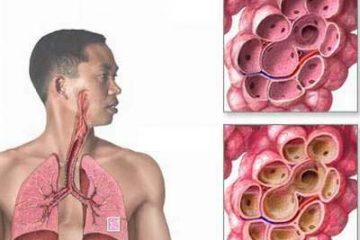

Là một bệnh lý của đường hô hấp trong đó niêm mạc của các phế quản trong phổi bị viêm. Niêm mạc phế quản bị kích thích sẽ phồng và dày lên và làm hẹp hoặc tắc nghẽn các tiểu phế quản, sẽ gây ra ho và có thể kèm theo đờm (đàm).